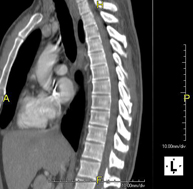

Prova radiològica que consisteix en obtenir imatges de les vèrtebres cervicals d'alta definició anatòmica, mitjançant l'ús d'un equip de TC (Tomografia Computeritzada). Indicacions: dolor cervical amb/sense irradiació als braços, traumatisme, malformacions congènites. - TC Columna dorsal

Prova radiològica que consisteix en obtenir imatges de les vèrtebres dorsals d'alta definició anatòmica, mitjançant l'ús d'un equip de TC (Tomografia Computaritzada). Indicacions: dolor dorsal, estudi de desviacions de la columna, traumatisme. - TC Columna lumbar

Prova radiològica que consisteix en obtenir imatges de les vèrtebres lumbars d'alta definició anatòmica, mitjançant l'ús d'un equip de TC (Tomografia Computaritzada). Indicacions: dolor lumbar sense / amb irradiació a les cames, dificultat per caminar, traumatisme. - TC de sacre-còccix